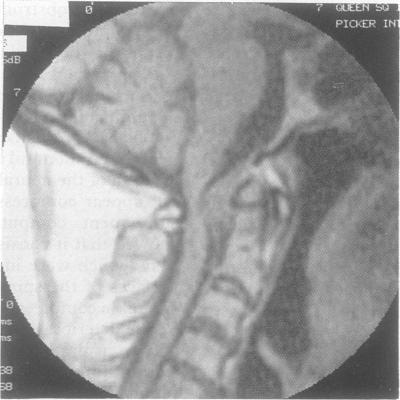

An extradural mass at the craniocervical junction causing progressive neurological disability in five elderly patients is described. The lesion, which might be confused with a meningioma or other tumour, is composed of amorphous degenerate fibrocartilaginous material and could be due to degeneration of the ligaments responsible for atlanto-axial stability. Recognition of the condition early is important as the patient's clinical condition will deteriorate without decompression. Anterior transoral removal is relatively simple, unlike surgery for tumours in the area, and will not destabilise the craniovertebral junction. It is likely that a proportion of these lesions are undetected, misdiagnosed or untreated to the detriment of the patient.